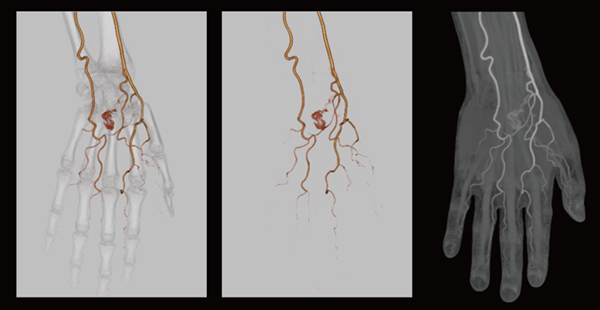

[CT 5300の臨床画像]

高画質CTA画像(Precise Image)

「Precise Imageによって以前よりもノイズが大幅に低減し,コントラストが向上しているため,3D画像の作成においては,ワークステーションによる骨や血管の自動抽出の精度が向上しました。末梢血管は通常,ノイズに埋もれてコントラストも付きにくく,3D画像の作成が非常に難しいのですが,現在は作成の手間が以前の半分以下になり,ストレスも軽減しています。また,頸部の撮影では肩のアーチファクトが劇的に低減し,鎖骨下動脈や肩周りの画像再構成が簡単に行えるようになりました」